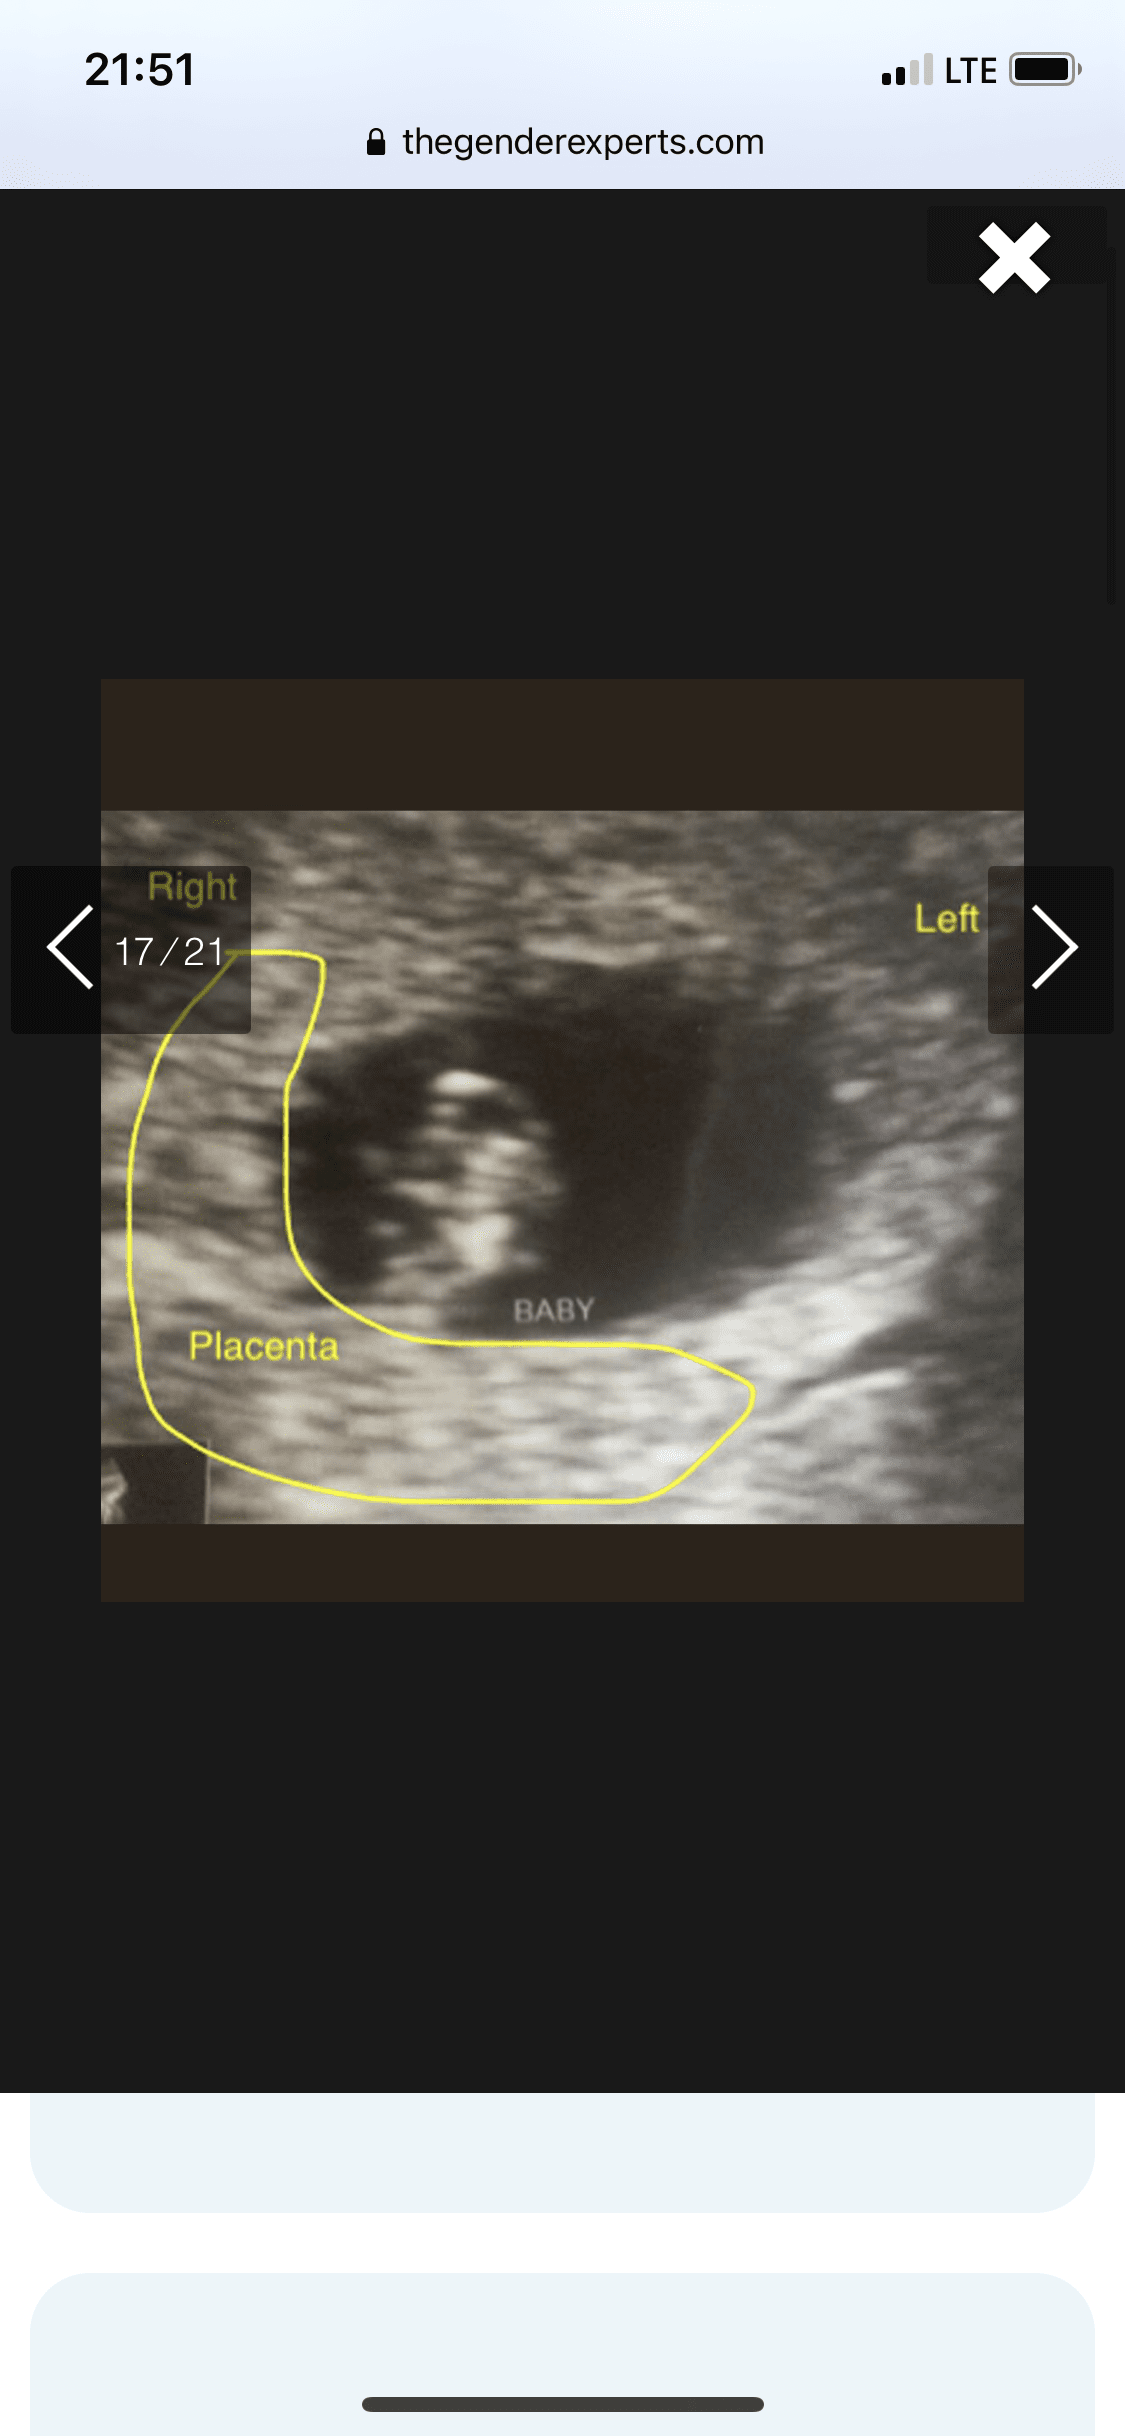

Tak dokładnie chodzi o położenie kosmowki z której potem wytworzy się łożysko. Metoda się sprawdza tak jak mówisz 50/50Aaa pytałam wtedy o położenie kosmowki.